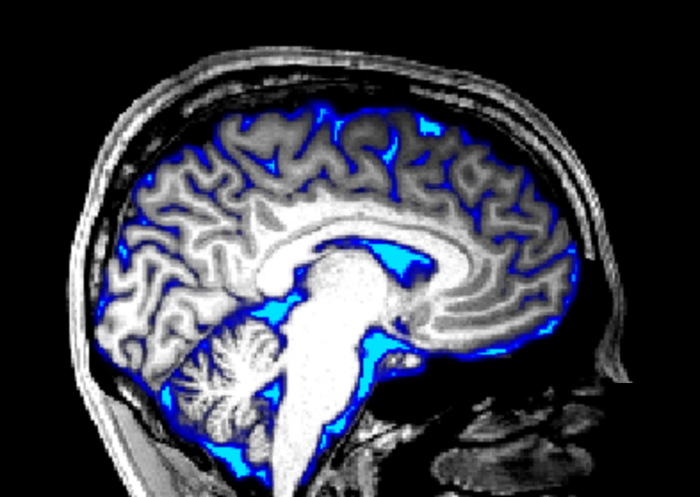

成人大脑MRI图像,脑脊液区域以蓝色覆盖。